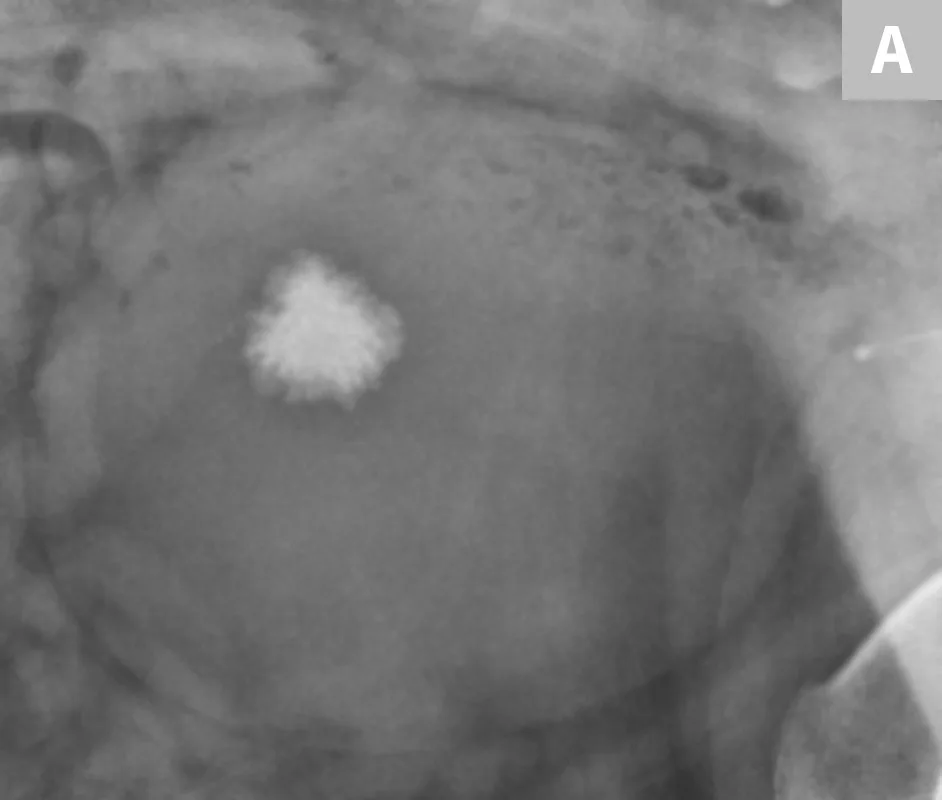

FIGURE 4A

Close-up radiograph of the left kidney in a dog with well-defined, linear regions of mineralization localized to renal diverticula.